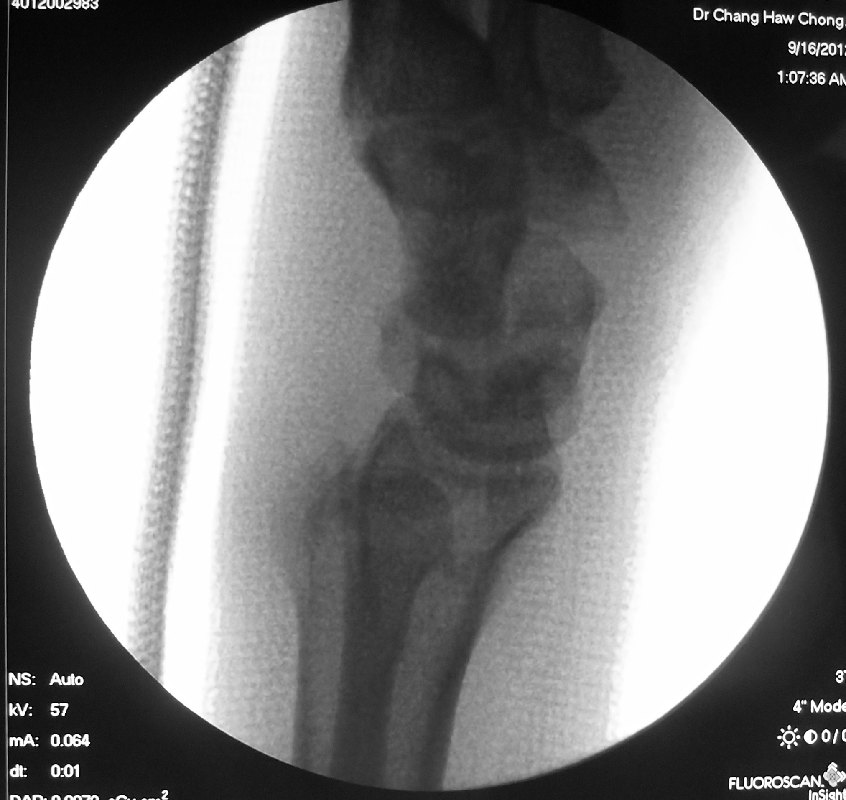

For definitive treatment of this injury, the patient required an open reduction and fixation of the scaphoid fracture together with reduction and stabilisation of the luno-triquetral joint to allow the lunotriquetral ligament to heal.

This is how the x-rays looked like after the surgery:

The fracture went on to heal over the next 2 to 3 months. This is how it looked like after the scaphoid fracture had healed.

The 2 wires along the luno-triquetral joint were surgically removed at 3 months after the surgery.